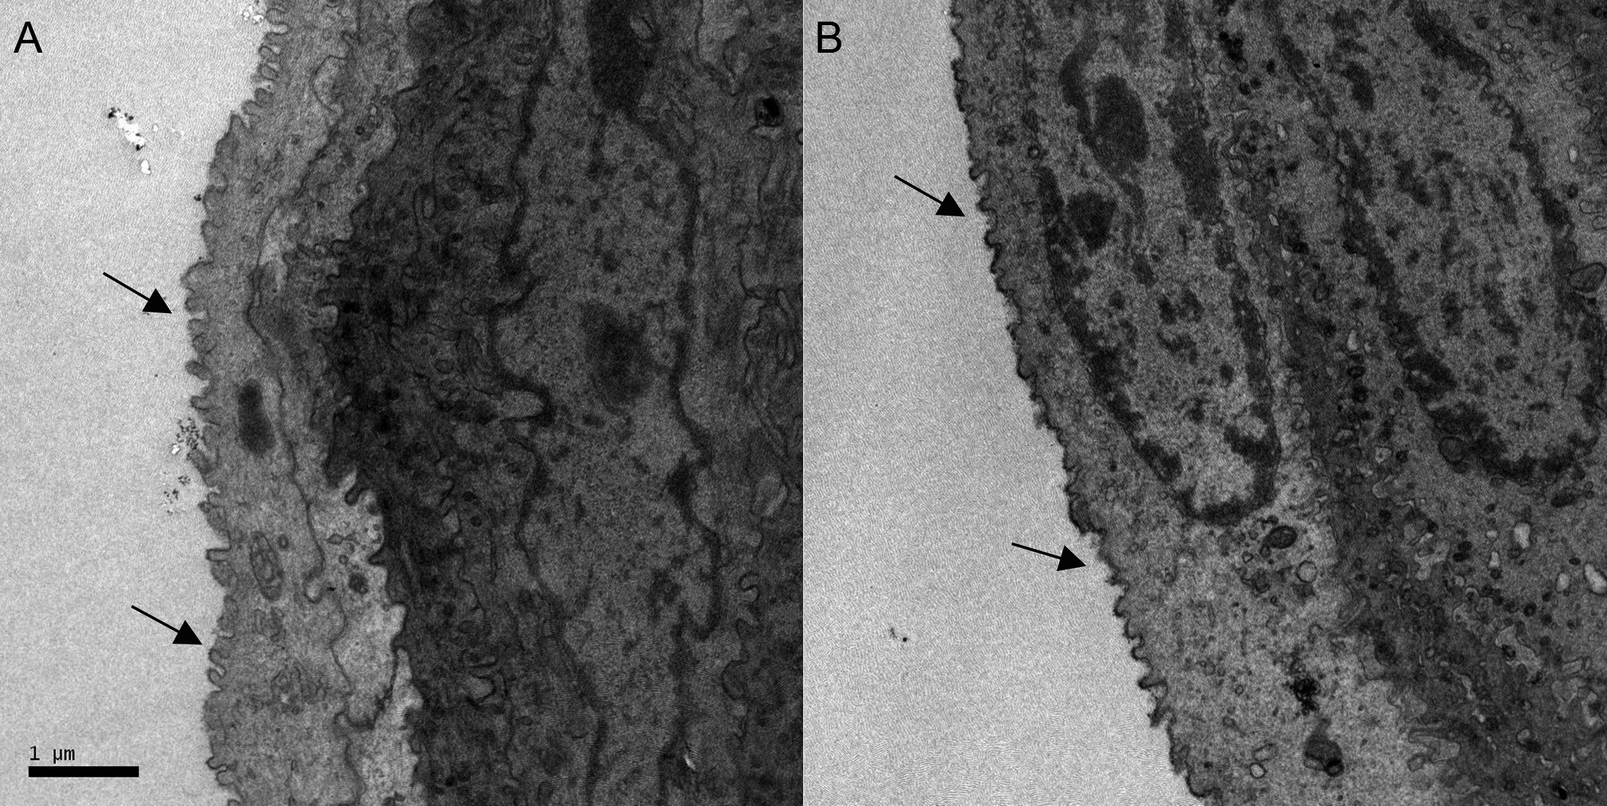

Figure 5. Representative images of

transmission electron microscopy. Shown are the flatten microvillis

with larger intervals between them on the cellular surface of

epithelium after BAC treatment (B, black arrows). The

microvillis were sharp with highdense in the control group (A,

black arrows).